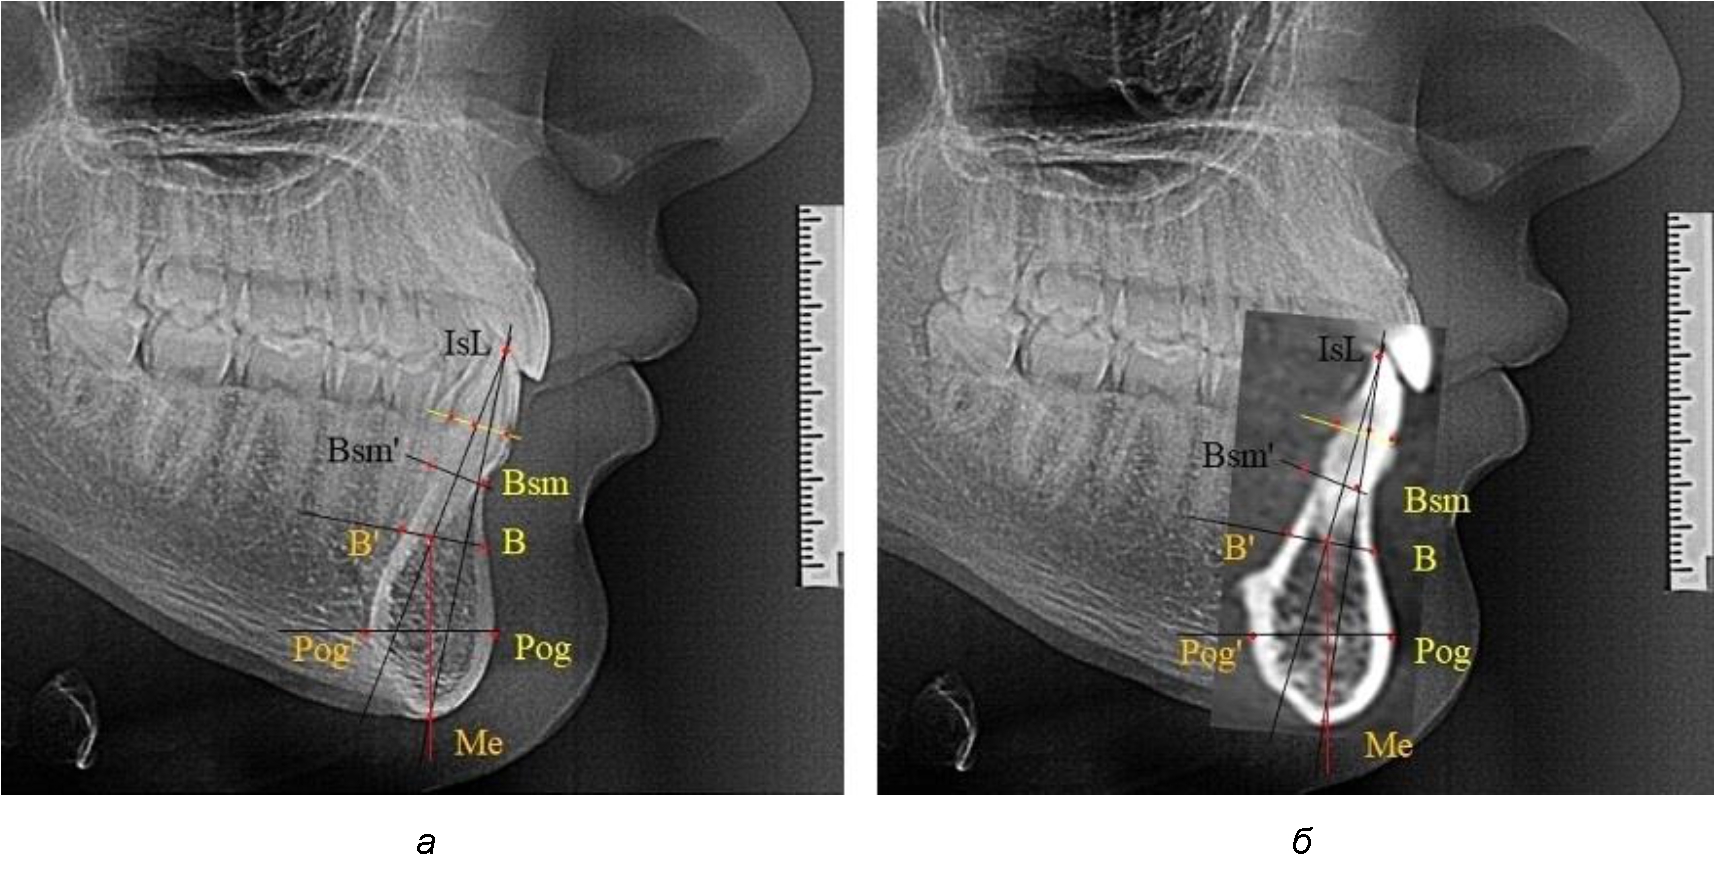

При аномалиях окклюзии в сагиттальном направлении и характерных для них различных вариантах протрузионного и/или ретрузионного патологического положения передних зубов, как правило, сопровождается изменениями параметров подбородочного выступа. Учитывая многообразие форм аномалий окклюзии, параметры подбородочного выступа вариабельны как по сагиттали, так и по трансверсали.

Нередко отмечается деформация подбородочного выступа и различное его положение по отношению к зубоальвеолярной части сегмента. При мезиальной окклюзии нередко нижняя подбородочная точка смещается кзади по отношению к условной срединной вертикали нижнего резца, а при дистальной окклюзии отмечается компенсаторное отклонение подбородка кпереди (рис. 5).

Рис. 5. Особенности нижнечелюстного резцового сегмента на ТРГ у людей при мезиальной (а) и дистальной (б) окклюзии

Кроме того, так же как и у людей с физиологической окклюзией, определялось различие в положении апикальных точек Downs и Schwarz, что, по нашему мнению, может определять тактику лечения патологических форм протрузии/ретрузии резцов с учетом биотипа костной ткани.